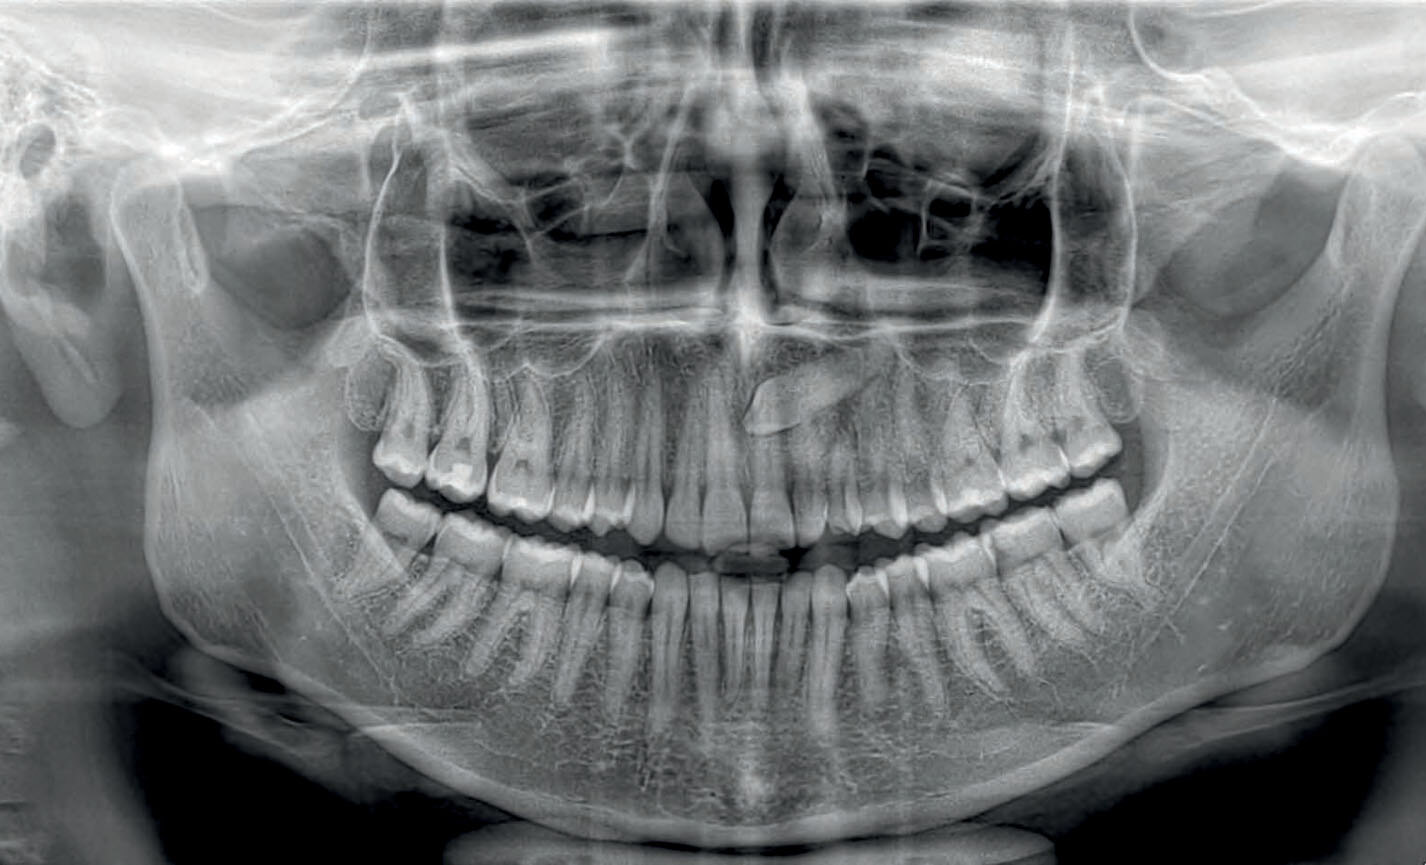

Orthopanoramiques

Panoramique rapide : dose faible et temps de balayage réduit, idéal pour des investigations primaires, le suivi, ou en cas de patients non collaborants.